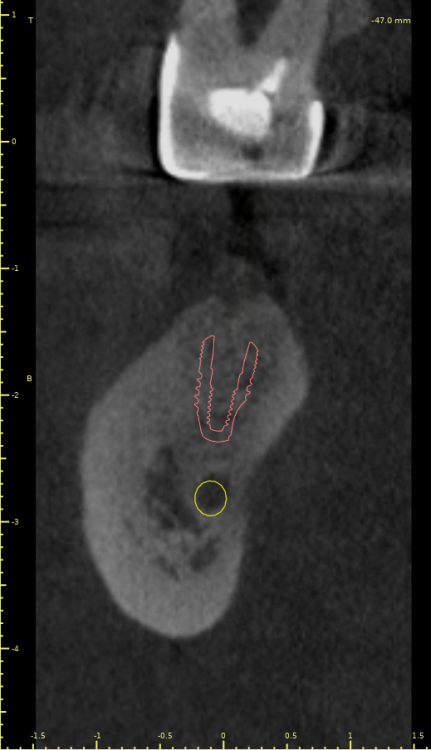

Коллеги, во время пилотного сверления как в области 4.5 так и в области 4.7 пациент отметил резкую боль. Если покрутить КТ, то как раз в местах планируемых имплантатов есть небольшие костные дефекты (хотя конечно на дефект это не тянет, тогда как называть?).

"Углубление" у 4.7

И у 4.5